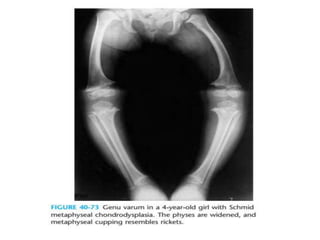

Schmid-type

• Autosomal dominant

• Mutations in type X collagen

• D/D - nutritional and vitamin D resistant rickets

normal serum chemistry values.

• Presents with

– leg pains

– varus knees and ankles

– short stature

– waddling gait